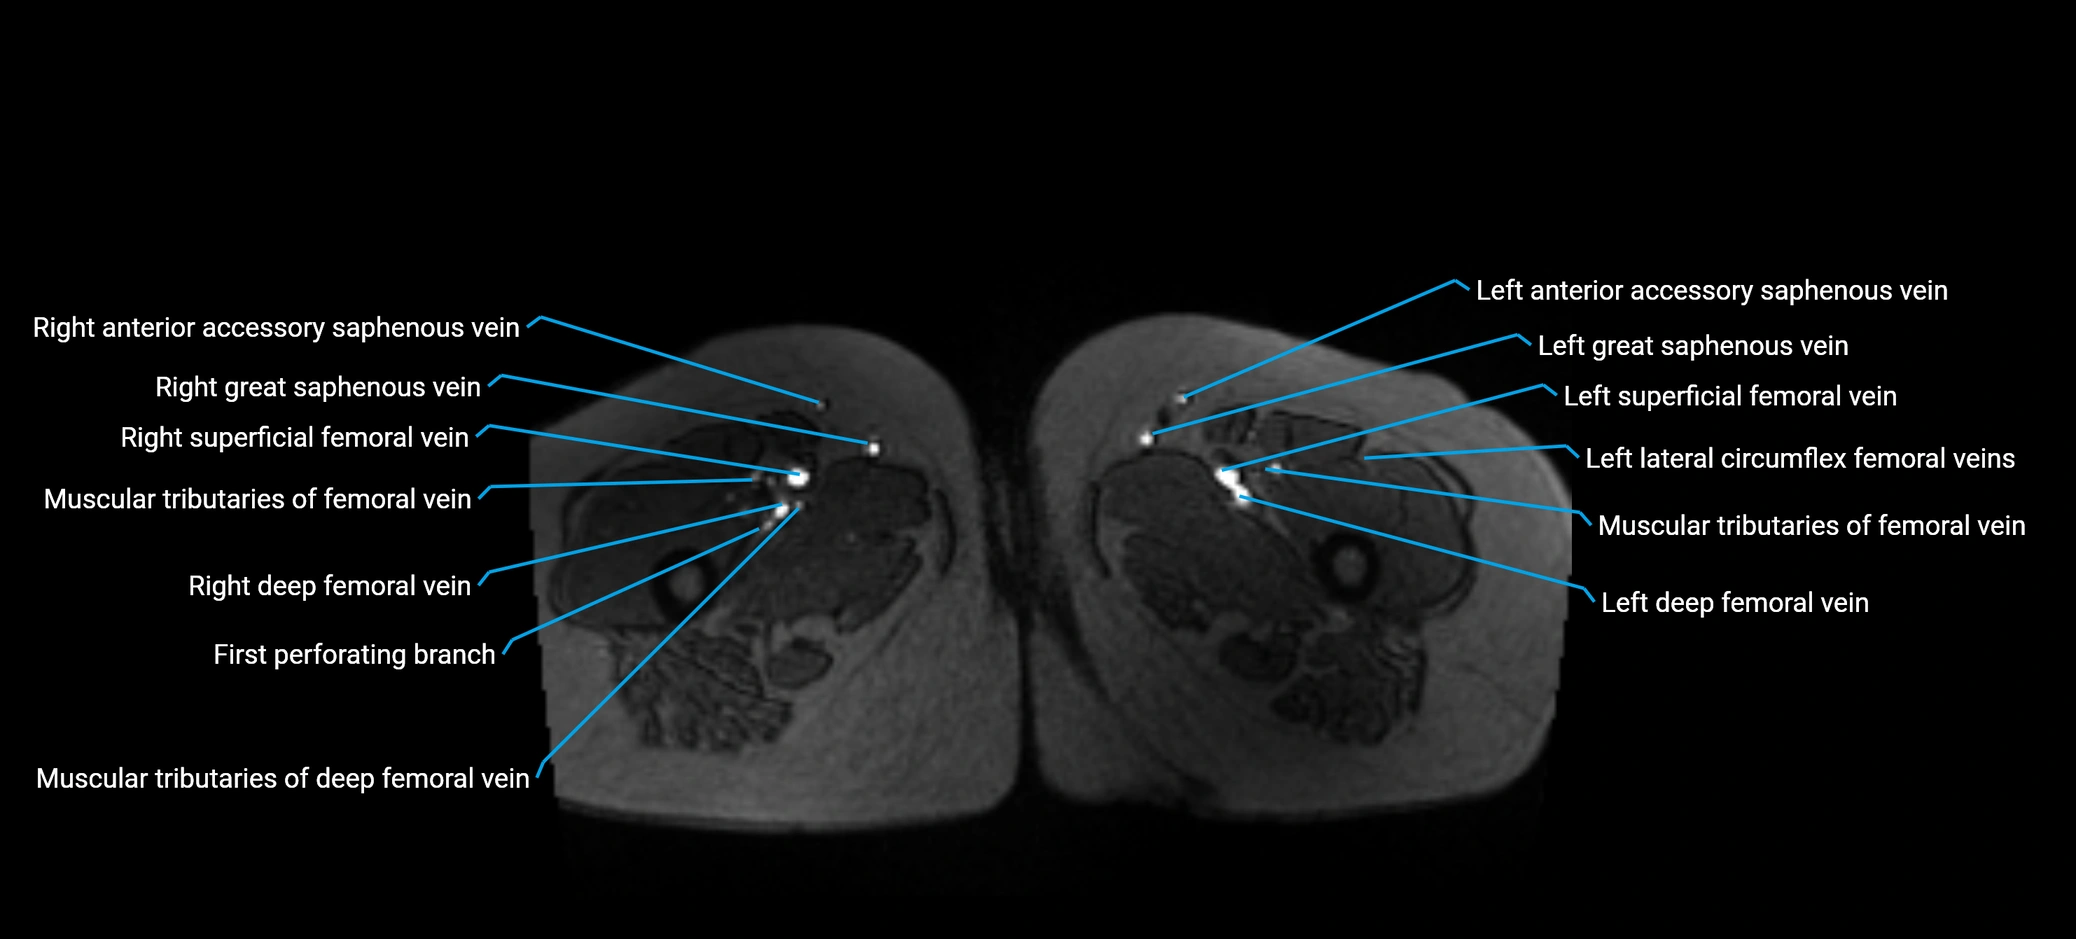

MRI image

image